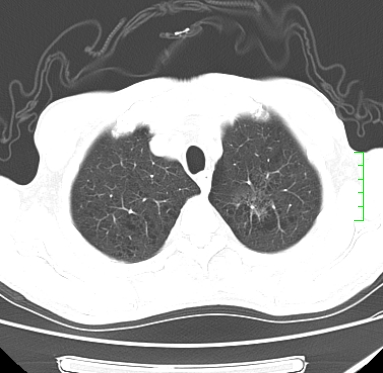

m,73y。膝关节疼痛伴双下肢水肿。入院常规胸片发现结节灶。增强为静脉期。

肿块周围可见局限性气肿,考虑肺癌可能性大。双肺上叶继发型肺结核。

指套征,强化明显,近侧肺组织局限性肺气肿,考虑支气管类癌,慢支、肺气肿、双上陈旧性tb、冠脉钙化。

鉴别:先天性支气管闭锁,变态反应性支气管肺曲霉菌病,肺癌,支气管囊肿,支扩黏液嵌塞。

1)考虑右肺下叶周围型肺癌。2)右肺上叶及左肺感染性病变(结核可能)。3)肺气肿。4)冠状动脉钙化。